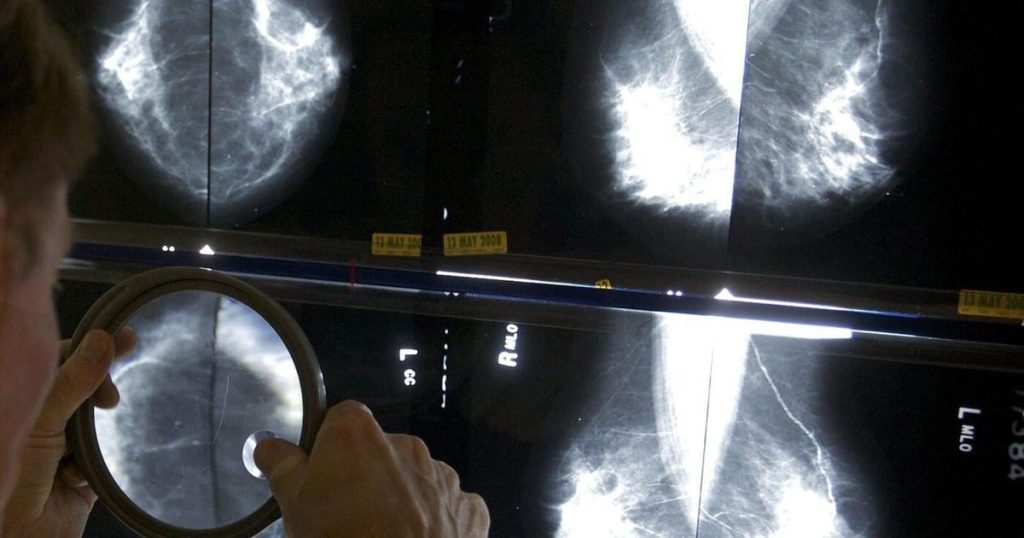

The group came under fire in May 2024 for rejecting expert advice to lower the age for breast cancer screening.

It maintained that routine breast cancer screening should start at age 50 and end after age 74, though it said younger women could seek a mammogram after weighing the risks and benefits of early screening.

Experts and the Canadian Cancer Society had called for the minimum screening age to be lowered to 40. A number of provinces are already funding screening for women between the ages of 40 and 50.